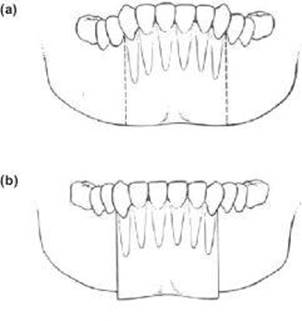

1. Take the vertical osteotomy cuts of the Kole down through the lower border to produce a three-part osteotomy of the mandible (Figure 9.9a). This enables a setdown which maintains or improves the lower facial height.

2. Combine the oblique advancement genioplasty cut with the two vertical segmental cuts, producing a four-part mandibuloto-genioplasty (Figure 9.9b). The anterior incisor segment is then set down and fixed as planned and will displace the genioplasty segment downwards and also allow advancement. These are not only simple solutions to anatomical difficulty but also increase the anterior inferior dentoalveolar height and improve the lower facial proportion. However, as the mandible has been completely divided bilaterally, dentoalveolar localisation is done with a deep wafer, an arch bar or supplemental archwire in distal tubes and the lower level by bone plates.

Figure 9.9 (a), (b)